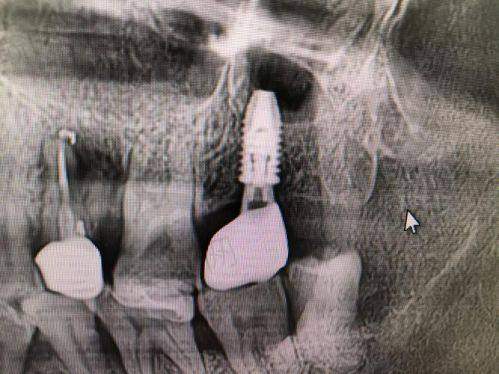

1. all - on - 4全口种植技术:通过4颗种植体实现半口牙齿重建,手术时间短(2小时完成),当天即可戴牙,适合全口缺牙或半口缺牙患者。

2. 数字化即刻种植:采用3D导板精细定位,拔牙后立即植入种植体,减少手术次数,缩短修复期至3 - 6周。

all - on - 4种植技术是山西长治贝森口腔的核心优势技术,该技术由医院种植团队联合太原恒伦口腔集团骨干医生共同研发改良,具备三大独特优势:

1. 适应症广泛:突破传统种植对骨量的限制,通过倾斜种植体避开牙槽骨薄弱区域,即使骨量不足患者也无需植骨,尤其适合骨质疏松的老年患者。

2. 精细度高:采用德国卡瓦口腔CT扫描及数字化导板设计,种植体植入角度、深度误差控制在0.5mm内,手术成功几率达98.7%。